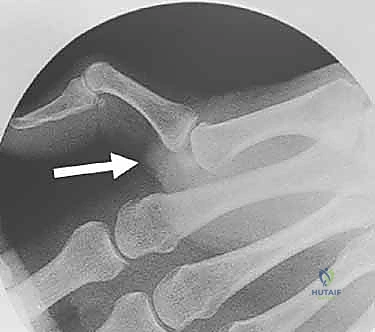

2. التصوير بالأشعة السينية (X-rays)

يُعد التصوير الشعاعي الخطوة الأولى لاستبعاد وجود كسور مصاحبة. في كثير من الأحيان، ينسلخ الرباط ويسحب معه قطعة صغيرة من العظم (Avulsion fracture). كما يتم أخذ صور أشعة تحت الإجهاد (Stress X-rays) لتوثيق عدم الاستقرار.

لتقييم الأنسجة الرخوة والأربطة بدقة متناهية، يتم اللجوء للرنين المغناطيسي. هذا الفحص حاسم جداً لاكتشاف ما يُعرف بـ آفة ستينر (Stener Lesion).

ما هي آفة ستينر (Stener Lesion)؟

تحدث هذه الحالة المعقدة عندما يتمزق الرباط الجانبي الزندي (UCL) بالكامل، وبدلاً من أن يبقى في مكانه ليلتئم، ينزلق الرباط الممزق ويصبح محاصراً فوق وتر عضلة أخرى (وتر العضلة المقربة للإبهام). هذا التداخل الميكانيكي يمنع التئام الرباط بشكل طبيعي تماماً، ويجعل التدخل الجراحي أمراً حتمياً لا مفر منه.